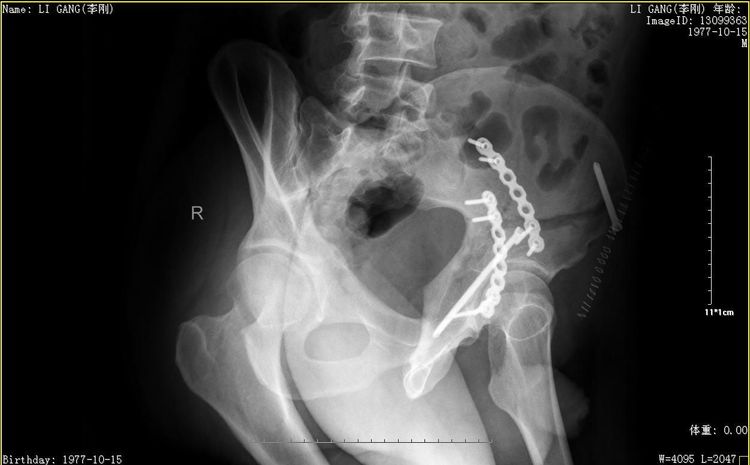

术后髂骨斜位

术后闭孔斜位